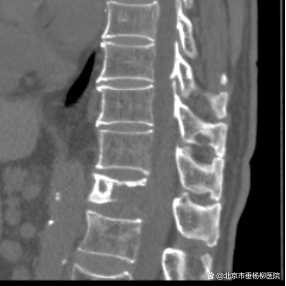

原来在一年前,黄老因罹患肾脏肿瘤行左肾切除术,但术后病理不详。脊柱外科(骨四科)主任姜树东在得知这一情况后,立即为患者完善胸腰椎核磁共振检查。结果提示T12椎体骨质破坏,结构不完整,向后压迫硬膜囊,椎管狭窄,脊髓受压;周围软组织肿胀;考虑病理性骨折(T12),脊柱转移瘤可能性大。随后,再行T12椎体穿刺活检术。同时患者家属提供了患者的既往病历:左肾肿瘤符合透明细胞癌。

▲术前检查

椎骨活检病理结果显示:(T12椎体内组织)送检少许破碎骨组织、多量纤维结缔组织及纤维素渗出坏死组织。纤维结缔组织部分间质疏松水肿,部分区域细胞密集,局灶可见透明细胞浸润。结合病史及免疫组化结果,符合肾透明细胞癌转移。